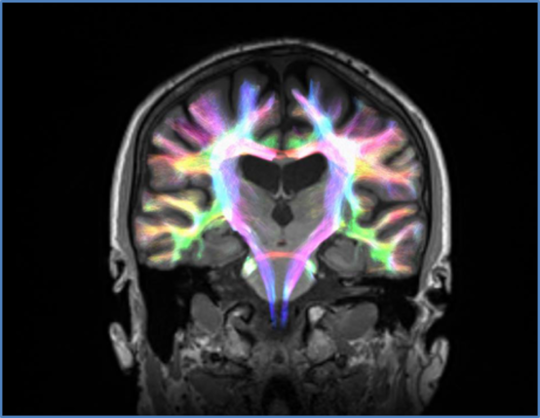

We used an advanced method of brain imaging called diffusion MRI, which allowed us to visualise the structure of connections between the different brain regions involved in these circuits. Using this technology, we could quantify if the strength of these connections had been affected by Parkinson’s disease.

We used diffusion imaging to study participants’ brain activity. Author provided

We used diffusion imaging to study participants’ brain activity. Author provided